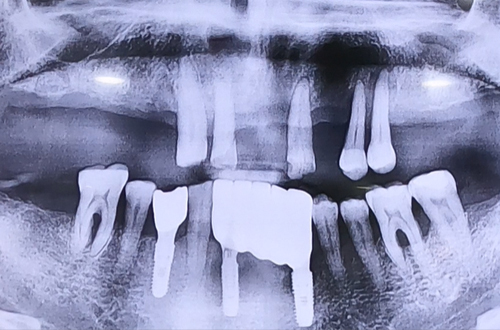

BEFORE

대부분의 윗니가 심하게 흔들린 후 빠진 상태이고,

남은 윗니들도 빠지기 직전인 상태로 내원하신 환자분입니다.

아랫니 상태는 양호하였으므로 상태가 많이 안 좋은 윗니의

전체 임플란트 치료를 진행하게 되셨는데요.

검사를 해 보니 오른쪽 위 송곳니는 단단하게 상태가 좋았으므로

해당 송곳니를 남겨두고 나머지 전체 임플란트를 하기로 결정했습니다.